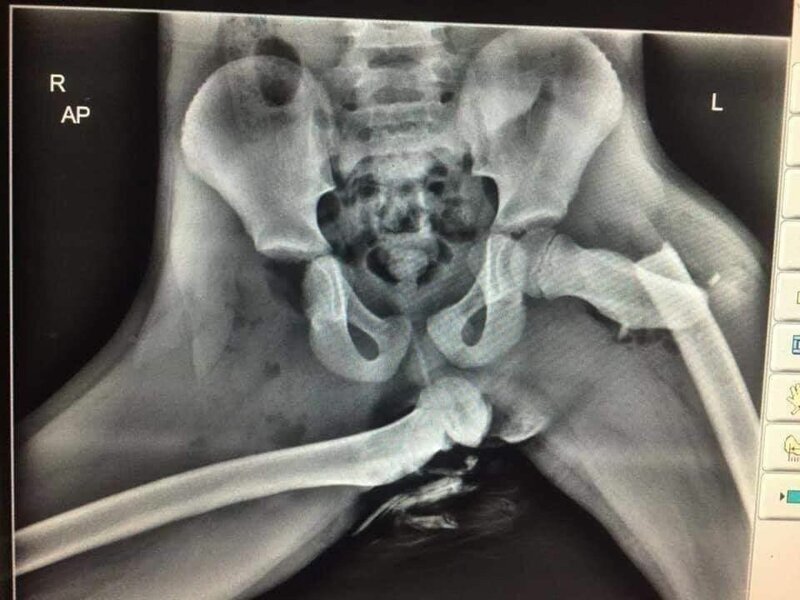

Как показал случай в Уэльсе, такое расположение в автомобиле может привезти к очень плачевным последствиям. ДТП произошло с 4 пассажирами в автомобиле. Трое из которых отделались легкими синяками, но американка Одра Татум, ехавшая на переднем сиденье получила 5 переломов ноги. Ноги ей сломала подушка безопасности. Помимо ног, у нее сломан нос, а нос ей сломала своя же коленка.

Рентгеновский снимок после ДТП